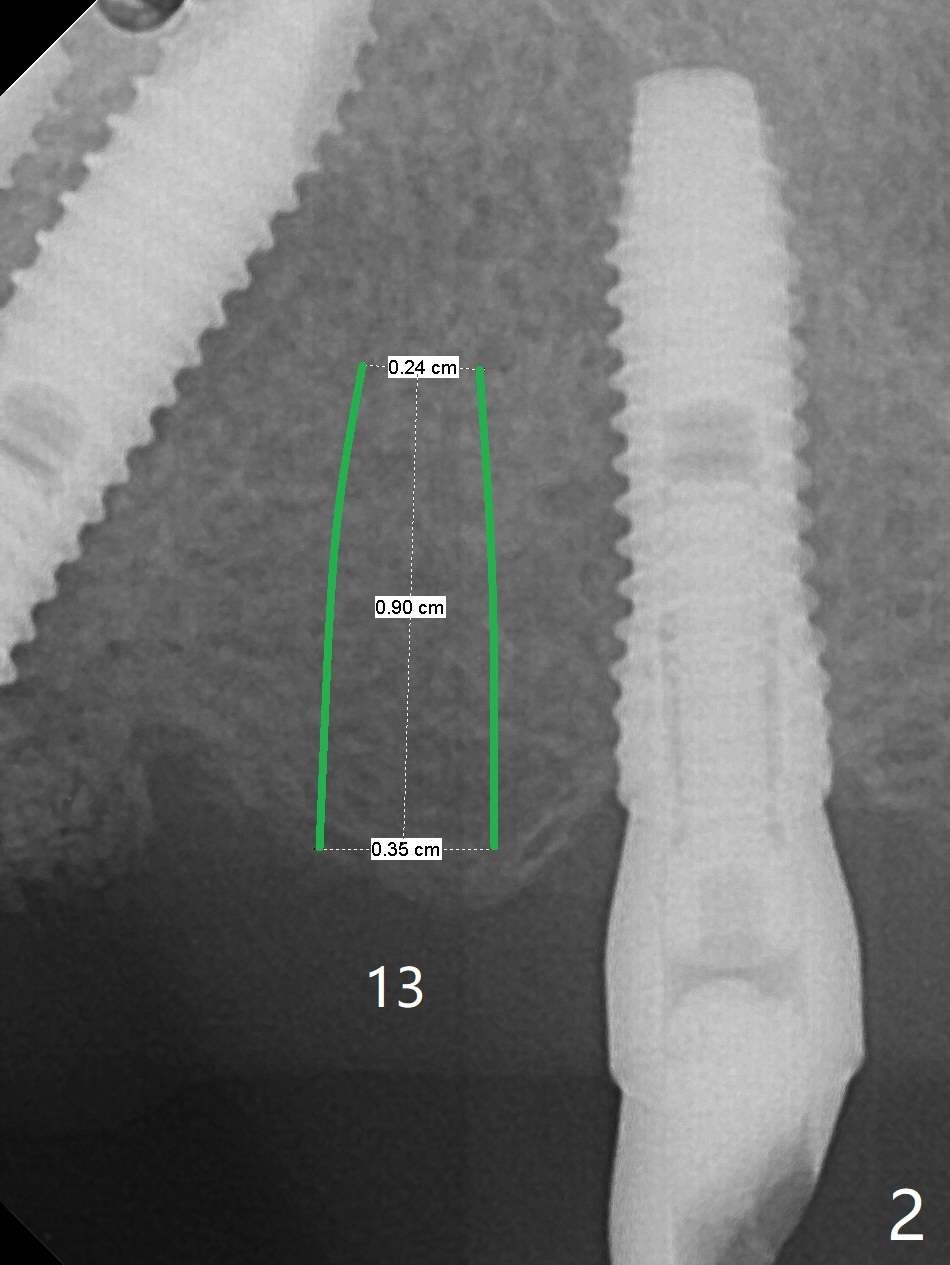

A 48-year-old man returns to clinic with fractured FPD 1 year 5 months post cementation (temp bond, Fig.1,7). It appears necessary to add an implant at #13 site (Fig.2). The narrow ridge is reduced to start an osteotomy (Fig.3 *). After change in osteotomy position and trajectory (Fig.4), a 3x10(4) mm 1-piece implant is placed (Fig.5). With deeper placement of the implant (Fig.6 arrow), cortical bone graft is placed (*).